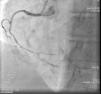

On admission the pain was decreasing; the physical examination was unremarkable, the electrocardiogram showed sinus rhythm, with negative T waves in the inferior leads, and troponin I was positive. The pain eventually disappeared after intravenous nitrates, and she was admitted to the coronary care unit. She underwent coronary angiography (Figure 1, Video 2), which revealed a spontaneous dissection of the posterior descending artery, with TIMI 2 flow, some posterolateral branches visualized from intercoronary collaterals, and severe vasospasm of the proximal right coronary artery (RCA), which reproduced the pain, relieved after intracoronary nitrates. No other unequivocal coronary lesions were noted, although a long dissection of the left anterior descending artery with intact intima cannot be excluded (Online Figure 2). It was decided not to perform percutaneous coronary intervention (PCI), and she was kept in the ward anticoagulated with subcutaneous enoxaparin (1 mg/kg twice daily), with dual antiplatelet therapy and a calcium channel blocker. Screening for autoimmune disease was negative. There were no events during hospitalization and she was scheduled for an angiographic review a week later, which showed progression of the dissection, with a wider false lumen (Figure 2, Video 3). Pain recurred during the procedure and a dissection was noted in a posterolateral branch. It was decided to perform PCI, and two bioabsorbable vascular scaffolds (BVS) were implanted in the PDA, guided by optical coherence tomography (OCT) coregistered with angiography. A third BVS was implanted in the distal RCA due to proximal progression of the dissection. A bare-metal stent was also implanted in the ostial RCA due to a traumatic dissection induced by the guiding catheter. Comparison of the images from angiography and OCT reveals a discrepancy in total (false plus true) diameter in the distal RCA (Figure 3, Video 4). After the procedure the patient was asymptomatic, although with a significant residual dissection in the RCA and posterolateral branch (Video 5). Anticoagulation was suspended and she was discharged five days later, with no further episodes of chest pain. Four months after this episode, she has had no recurrence of pain and is asymptomatic.

Figure 1.

First angiogram of the right coronary artery (RCA), showing a long spontaneous coronary artery dissection from the distal RCA to the distal posterior descending artery and posterolateral branches.